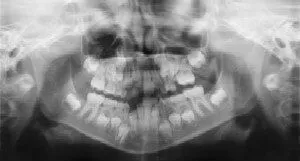

Radiographs (X-Rays) are a vital and necessary part of your child’s dental diagnostic process. Without them, certain dental conditions can and will be missed.

Radiographs detect much more than cavities. For example, radiographs may be needed to survey erupting teeth, diagnose bone diseases, evaluate the results of an injury, or plan orthodontic treatment. Radiographs allow dentists to diagnose and treat health conditions that cannot be detected during a clinical examination. If dental problems are found and treated early, dental care is more comfortable for your child and more affordable for you.

The American Academy of Pediatric Dentistry recommends radiographs and examinations every six months for children with a high risk of tooth decay. On average, most pediatric dentists request radiographs approximately once a year. Approximately every 3 years, a complete set of radiographs, either a panoramic and bitewings or periapicals and bitewings, is often recommended.

Pediatric dentists are particularly careful to minimize the exposure of their patients to radiation. With contemporary safeguards, the amount of radiation received in a dental X-ray examination is extremely small. The risk is negligible. In fact, the dental radiographs represent a far smaller risk than an undetected and untreated dental problem. Lead body aprons and shields will protect your child. Today’s equipment filters out unnecessary x-rays and restricts the x-ray beam to the area of interest. Digital X-rays and proper shielding assure that your child receives a minimal amount of radiation exposure.